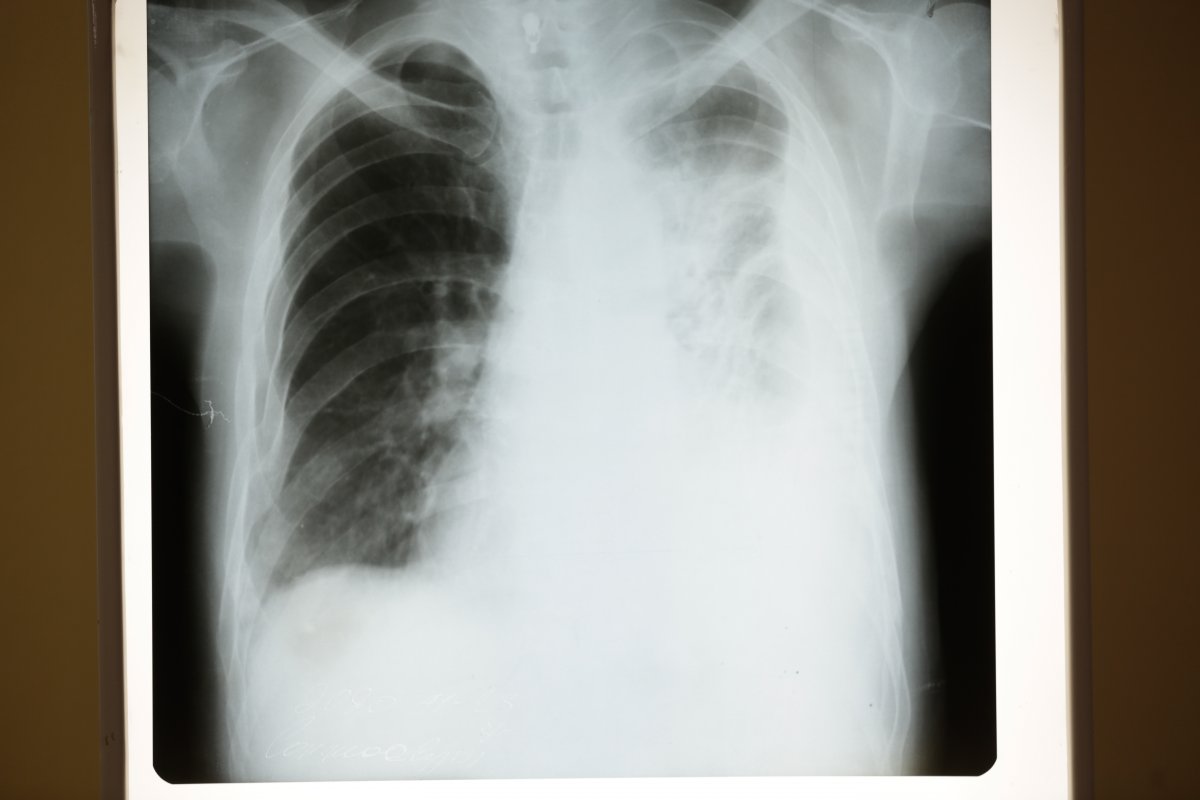

-Та бүхэнд энэ өдрийн мэндийг хүргэе. Сүрьеэ өвчний талаар ард иргэд маань сүүлийн үед мэдээлэл сайтай, мэдлэгтэй болж, шинж тэмдгийг нь сайн мэддэг болсон. Өөрөөр хэлбэл ханиалгадаг, цээжээр өвддөг, цэр гардаг, турж эцдэг, ядардаг, хөлөрдөг гэх зэрэг шинж тэмдгийн зовиуруудыг хүмүүс мэддэг болсон. Гэхдээ сүрьеэ өвчний хамгийн чухал нь амьсгалын замаар хүнээс хүнд дамждаг өвчин. Нэг халдвартай хэлбэрийн сүрьеэтэй өвчтөн жилд дунджаар 15-20 хүнд идэвхтэй хэлбэрийн сүрьеэгийн халдварыг тараах магадлалтай.

Одоо бид ковид-19 өвчний талаарх мэдээлэлтэй болсон. Энэ бол амьсгалын замаар халддаг өвчин, гараа угаах, маскаа зүүх ёстой, зайгаа барих ёстой гэх зэрэг мэдээлэлтэй болсон. Тэгвэл сүрьеэ өвчин ч гэсэн нэг талдаа ковид -19-ийн удаашруулсан хувилбар гэсэн үг. Нян нь удаан өснө, шинж тэмдэг нь удаан илэрнэ, эмчилгээ удаан явна. Тэрнээс биш гэмтээж байгаа эрхтний хувьд адилхан.

-Глобаль сангийн дэмжлэгтэй ДОХ, сүрьеэгийн төслийн хүрээнд Эрүүл сүрьеэгүй ирээдүйн төлөө ТББ-аас хэвтэрт байгаа, эмнэлэгт очиж эмээ уух боломжгүй сүрьеэгээр өвдсөн зорилтот бүлгийн хүмүүсийн гэрт нь очиж эмийг нь уулгах, эмчилгээнд хяналт тавих ажлыг зохион байгуулан ажиллаж байна. Энэ нь маш олон давуу талтай. Яагаад гэвэл, эмэнд тэсвэртэй сүрьеэ манайд 2006 оноос хойш оношлогдоод, эмчлэгдэж эхэлсэн. Сүрьеэ өвчин нь шинж тэмдэг адилхан боловч оношилгооны хувьд хоёр янз байгаа. Эмэнд мэдрэг сүрьеэ, эмэнд тэсвэртэй сүрьеэ.

Харин эмэнд тэсвэртэй сүрьеэ гэдэг нь хамгийн анхны хөнгөн хэлбэрийн эмчилгээ нь үр дүнгүй болдог эсвэл хүндэрдэг цаашлаад сүрьеэгийн үндсэн эмчилгээнд хэрэглэдэг эмүүд тухайн хүнд үйлчлэхээ болиод эхлэхийг хэлж байгаа юм. Эсвэл тухайн хүн анхдагчаар эмэнд тэсвэртэй сүрьеэгийн нянгаар халдварлагдсан байж болно.